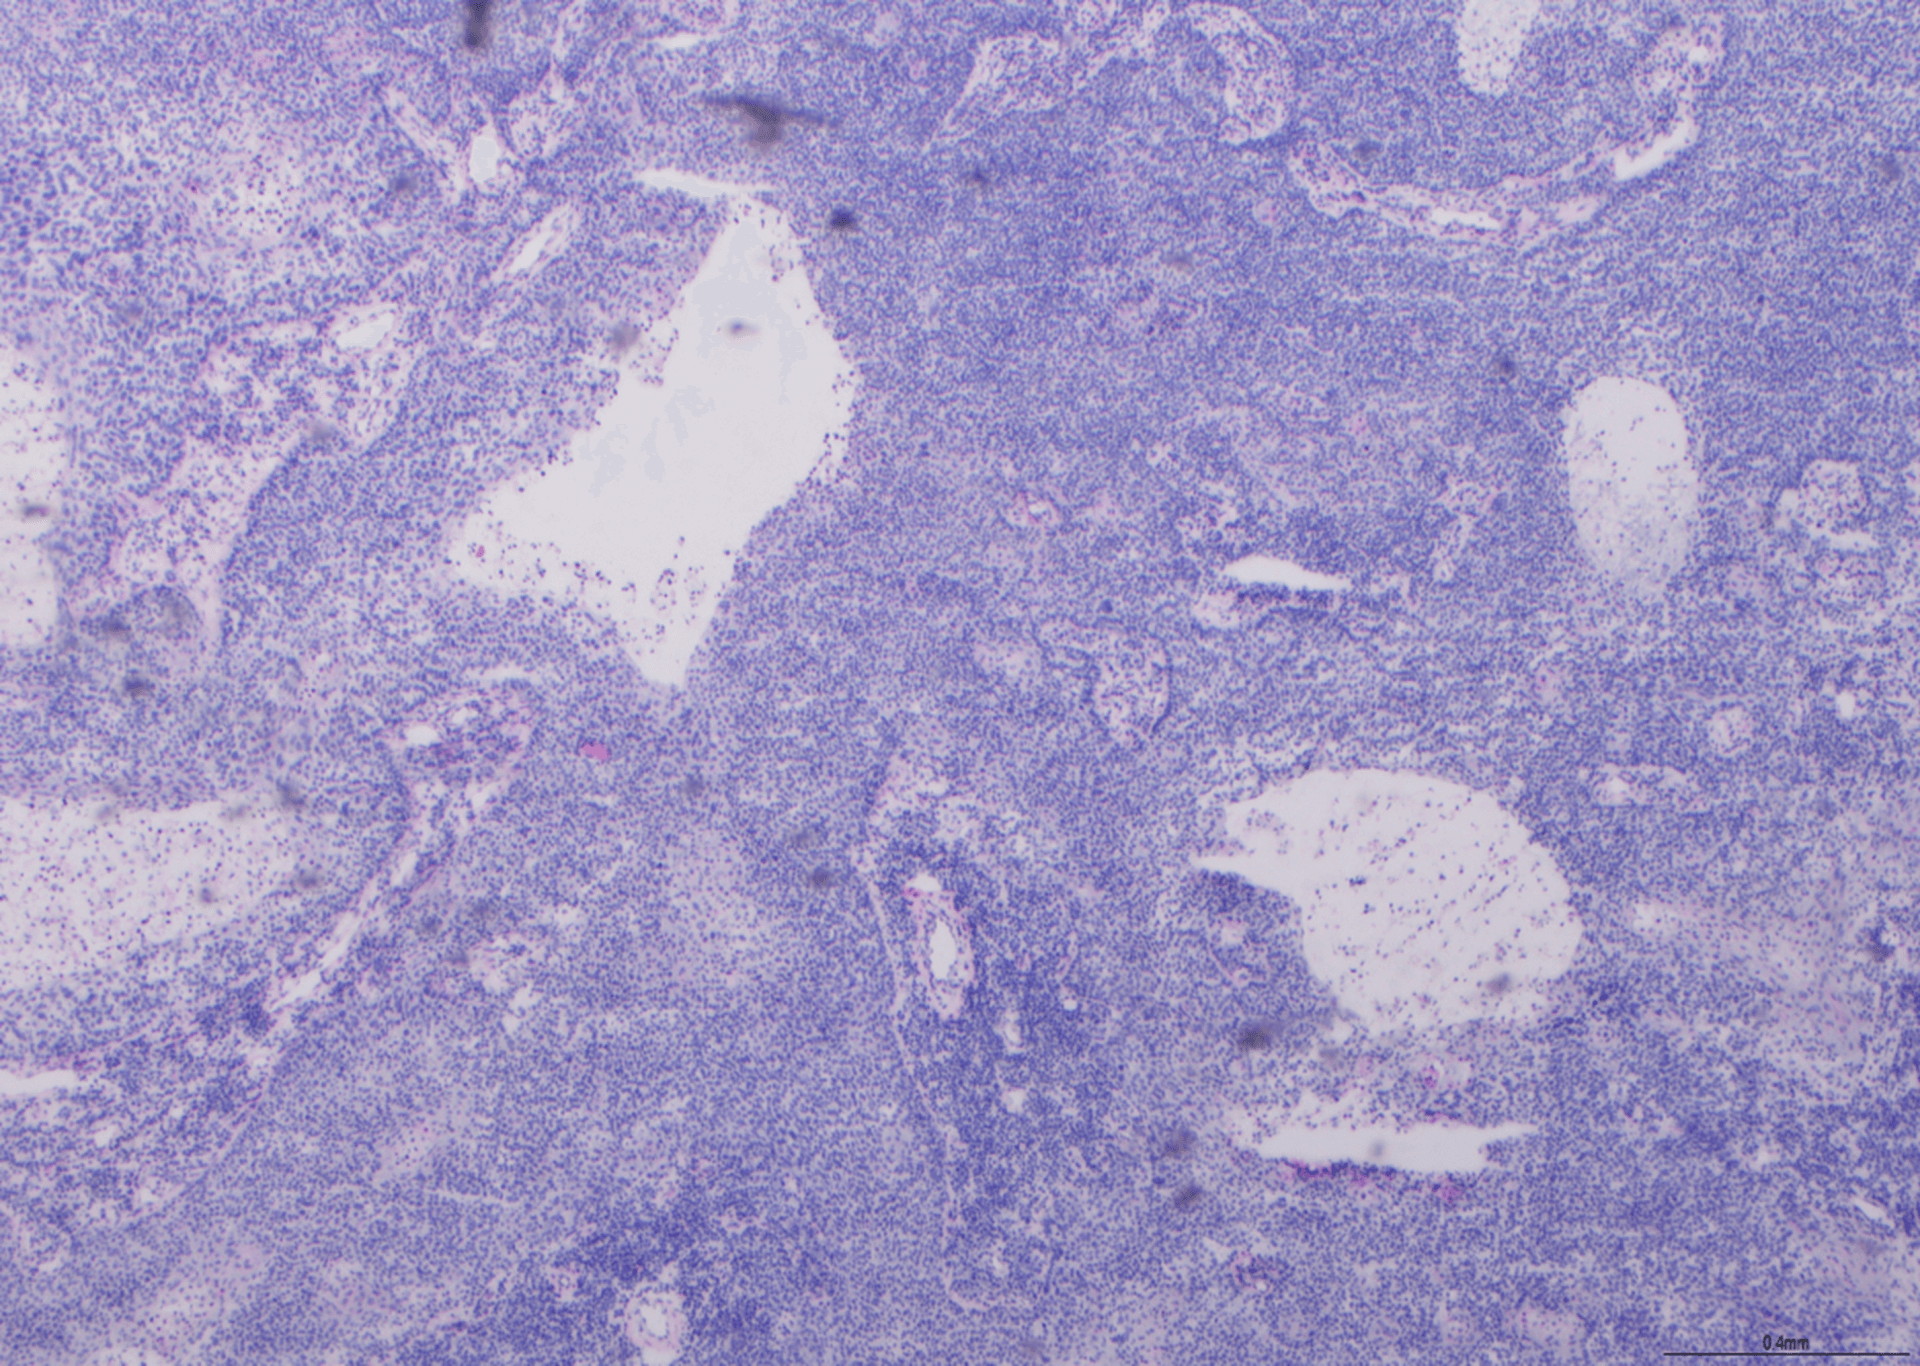

H E - Esquema BMT

Visto em x20. No geral, uma preparação muito boa, mas foram deduzidas notas por dobras e vincos, perda de material e coloração de fundo com hematoxilina. Esta lâmina obteve nota 8/10.